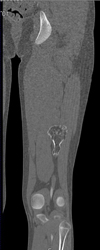

Diagnosis

Exostosis